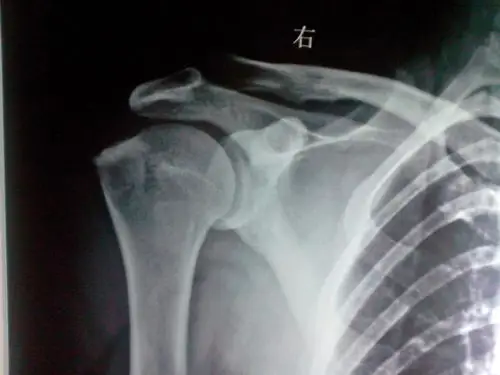

一张肩关节的片子